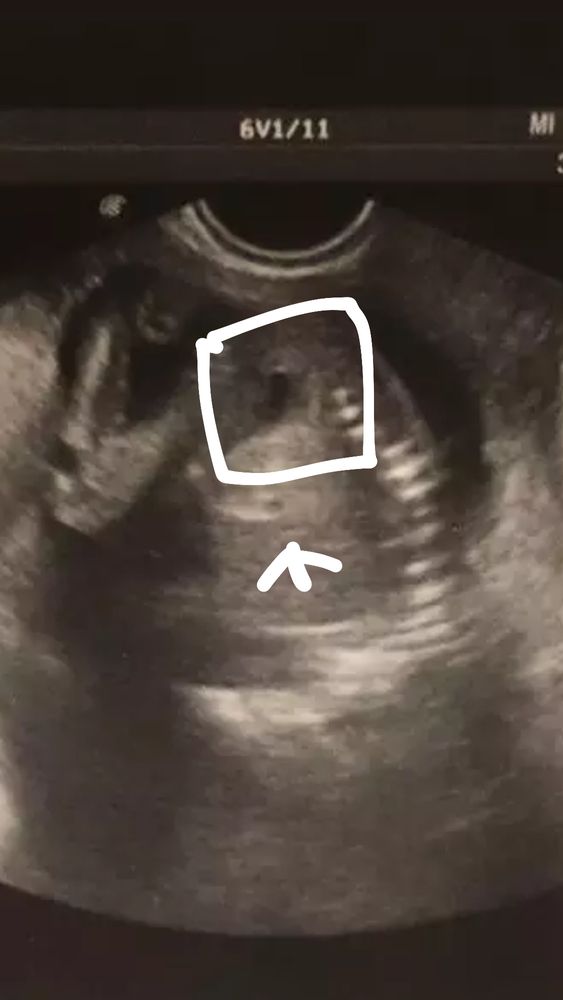

Изображение Во. Как видите оч похоже на мальчика, но мб еще девочка не доформировалась.,

Tereza Am, но справедливости ради ракурсы с пипиркой есть 🤣 даже два, третье узи разобрать уже не смогла 🤣